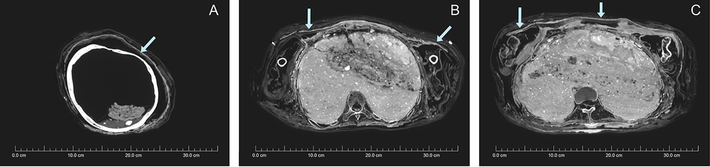

Gần đây, nhà khảo cổ Karin Sowada (Đại học Macquarie, Australia) dẫn đầu một nhóm chuyên gia có phát hiện lớn. Nhóm của ông phát hiện xác ướp được bọc bằng bùn trông như chiếc kén. Đây là điều rất hiếm gặp.

Sau khi qua đời, người phụ nữ được ướp xác và quấn nhiều lớp vải. Thi hài này đầu gối trái và cẳng chân bị phá hủy có thể là do những tên trộm mộ gây ra. Vì vậy, con cháu của người chết đã bọc lại xác ướp và trát bùn xung quanh.

Lần này, những người thợ dùng hỗn hợp phức tạp gồm bùn, cát và rơm giữa các lớp vải quấn bằng lanh. Lớp phủ nền có chất tạo màu từ calcite trắng trong khi lớp trên cùng phủ đất son, một loại khoáng chất màu đỏ.

Khi trát lên xác ướp, lớp bùn vẫn còn ẩm và dễ uốn nặn. Từ đó, xác ướp có hình dáng giống chiếc kén.